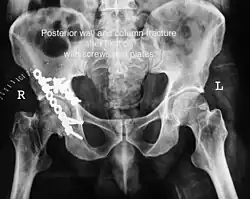

Posterior wall fracture fixed with screws and plate -

The final management depends on the size of the fragment(s), stability and congruence of the joint. In some cases traction for six to eight weeks may be the only treatment required; however, surgical fixation using screw(s) and plate(s) may be required if the injury is more complex. The latter treatment will be called for if bone fragments do not fall into place, or if they are found in the joint, or if the joint itself is unstable.

Implants : normally lag screws and reconstruction plates are preferred implants